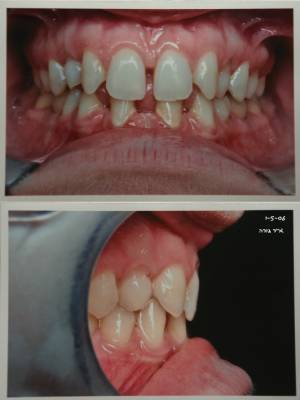

motivation esthetique(espaces!) renforcee par la soudaine mobilite des canines sup deciduelles

tu ne toucherais pas au maxillaire sup mais les canines lacteales vont tomber sous peu

aux vues de la pano et de la photo intrabuccale,je ne pense pas qu'il y ait assez de place pour un implant (vous confirmez les implantos?),il faudra certainement ouvrir en reculant un peu les 4 et fermant les espaces anterieurs

mais est ce que les bridges colles vont resister aux contraintes occlusales ? elle est plutot brachy et l'angle interincisif tres ouvert...

et au niveau esthetique,on aura des petites canines sup et des petites laterales inf:si je n'ouvre pas un peu tout ca,il me reste maximum 5 mm pour caser les 32 et 42,autant faire comme daniel le propose et placer une seule incisive?